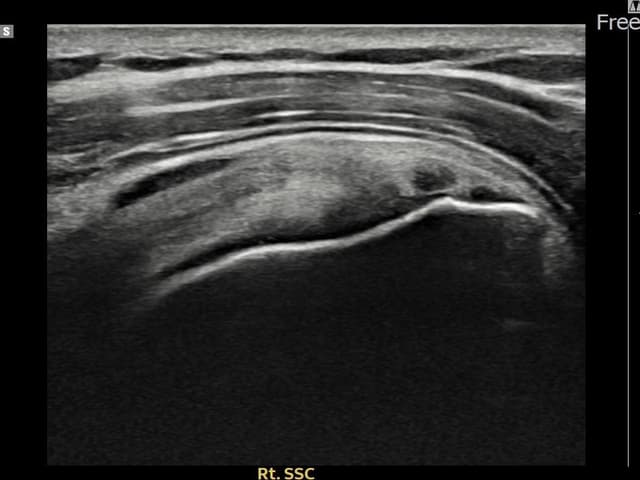

右侧 견갑하근건 关节面侧部分撕裂

7mm × 3mm (肌腱厚度约28%缺损)

右侧 견갑하근건 部分撕裂

8mm × 3mm (肌腱厚度约32%缺损)